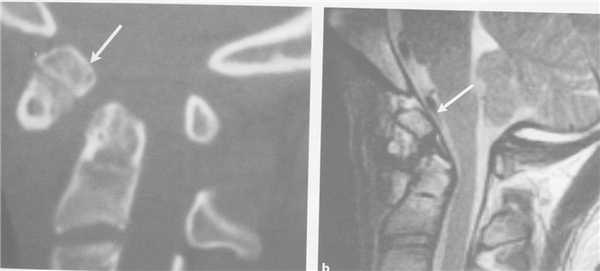

Пациент молодой человек 1992г.р., получил травму вследствие падения с высоты около 3 метров. Почувствовал резкую боль в шейном отделе позвоночника. Был доставлен в ближайшую больницу, где выполнена рентгенография шейного отдела позвоночника и выявлена переломо - вывих в атланто - аксиальном сочленении, перелом зубовидного отростка (РИС 1). С целью дообследования и нейрохирургического лечения пациент переведен в нашу клинику. Состояние при поступлении: Общее состояние удовлетворительное. Кожа чистая, обычной окраски. Отеков нет. Над легкими везикулярное дыхание, хрипов нет. Тоны сердца ясные, ритм правильный. АД 130/70 мм рт. ст. ЧСС - 76 в минуту. Живот при пальпации мягкий, безболезненный во всех отделах. Неврологический статус: В сознании, контактен, адекватен. Менингиальной симптоматики нет. Движения глаз в полном объёме. Зрачки по средней линии, равновеликие, фотореакция живая. Лицо симметричное. Чувствительность на лице не изменена. Глотание, фонация сохранены. Язык по средней линии. Пальценосовую пробу выполняет удовлетворительно с двух сторон. Тазовые функции контролирует. Движения в шейном отделе позвоночника ограничены, болезненны. Сухожильные рефлексы D=S.

С целью уточнения соотношения костных структур со спинным мозгом и выявления очагов ушиба в спинном мозге выполнена МРТ шейного отдела позвоночника и кранио - вертебрального перехода. Патологических изменений в спинном мозге не выявлено, между костными структурами и спинным мозгом сохраняется ликворное пространство.

При контрольных КТ шейного отдела позвоночника через 1 месяц и через 3 месяца удовлетворительное стояние позвонков и металлоконструкции.

В нашем случае была выбрана тактика репозиции в галло - аппрарате. На наш взгляд репозиция в условиях операционной при присутствии анестезиолога под ренетгенологическим контролем позволяет максимально безопасно выполнить сопоставление как отломков зубовидного отростка, так и атланто - аксиального комплекса, и при этом контролировать неврологический статус пациента. После достижения рентгенологически адекватной репозиции голова фиксирована в соответствующем положении в галло - аппарате и выполнена КТ исследование, что подтверждает хорошую репозицию как зубовидного отростка так и атланото - аксиального комплекса.